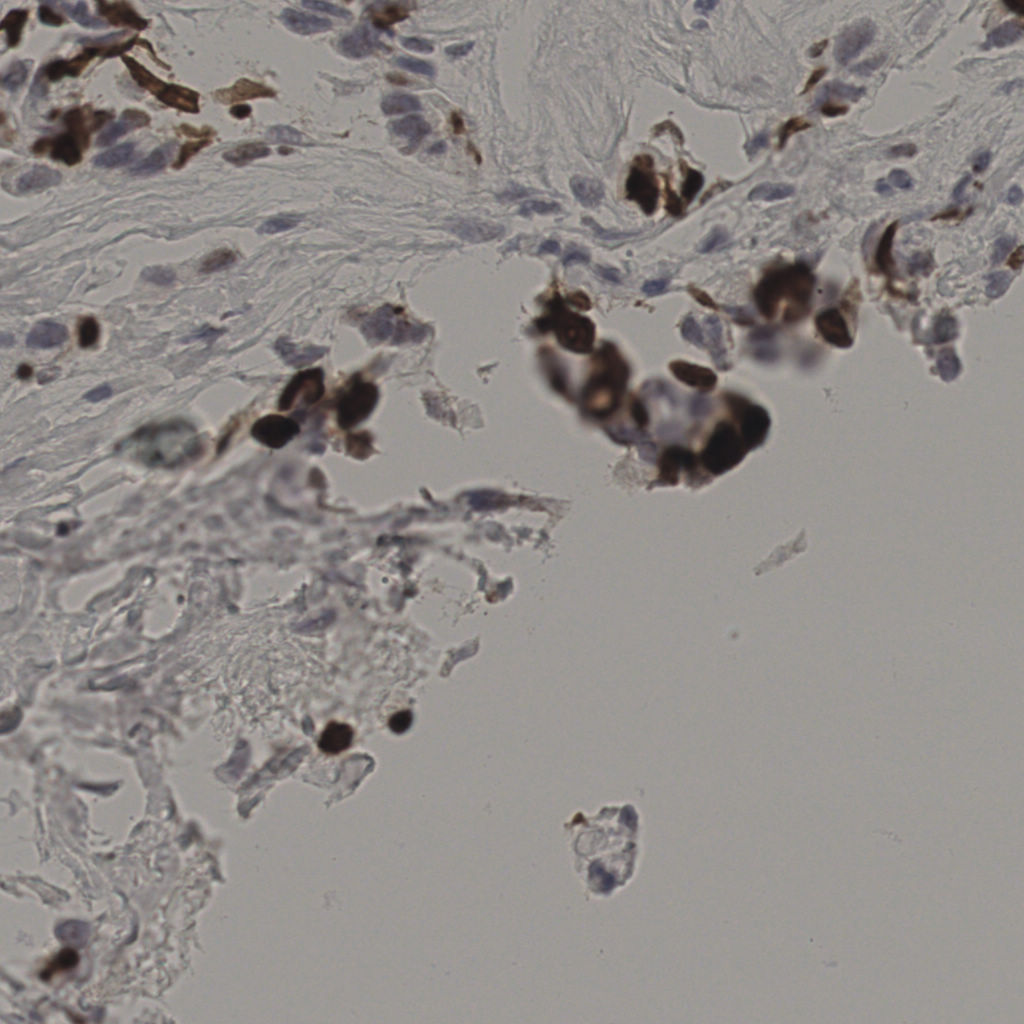

17.75%

Ki67 指数

阴 7986 阳 1723

20240285Ki-67.ndpi